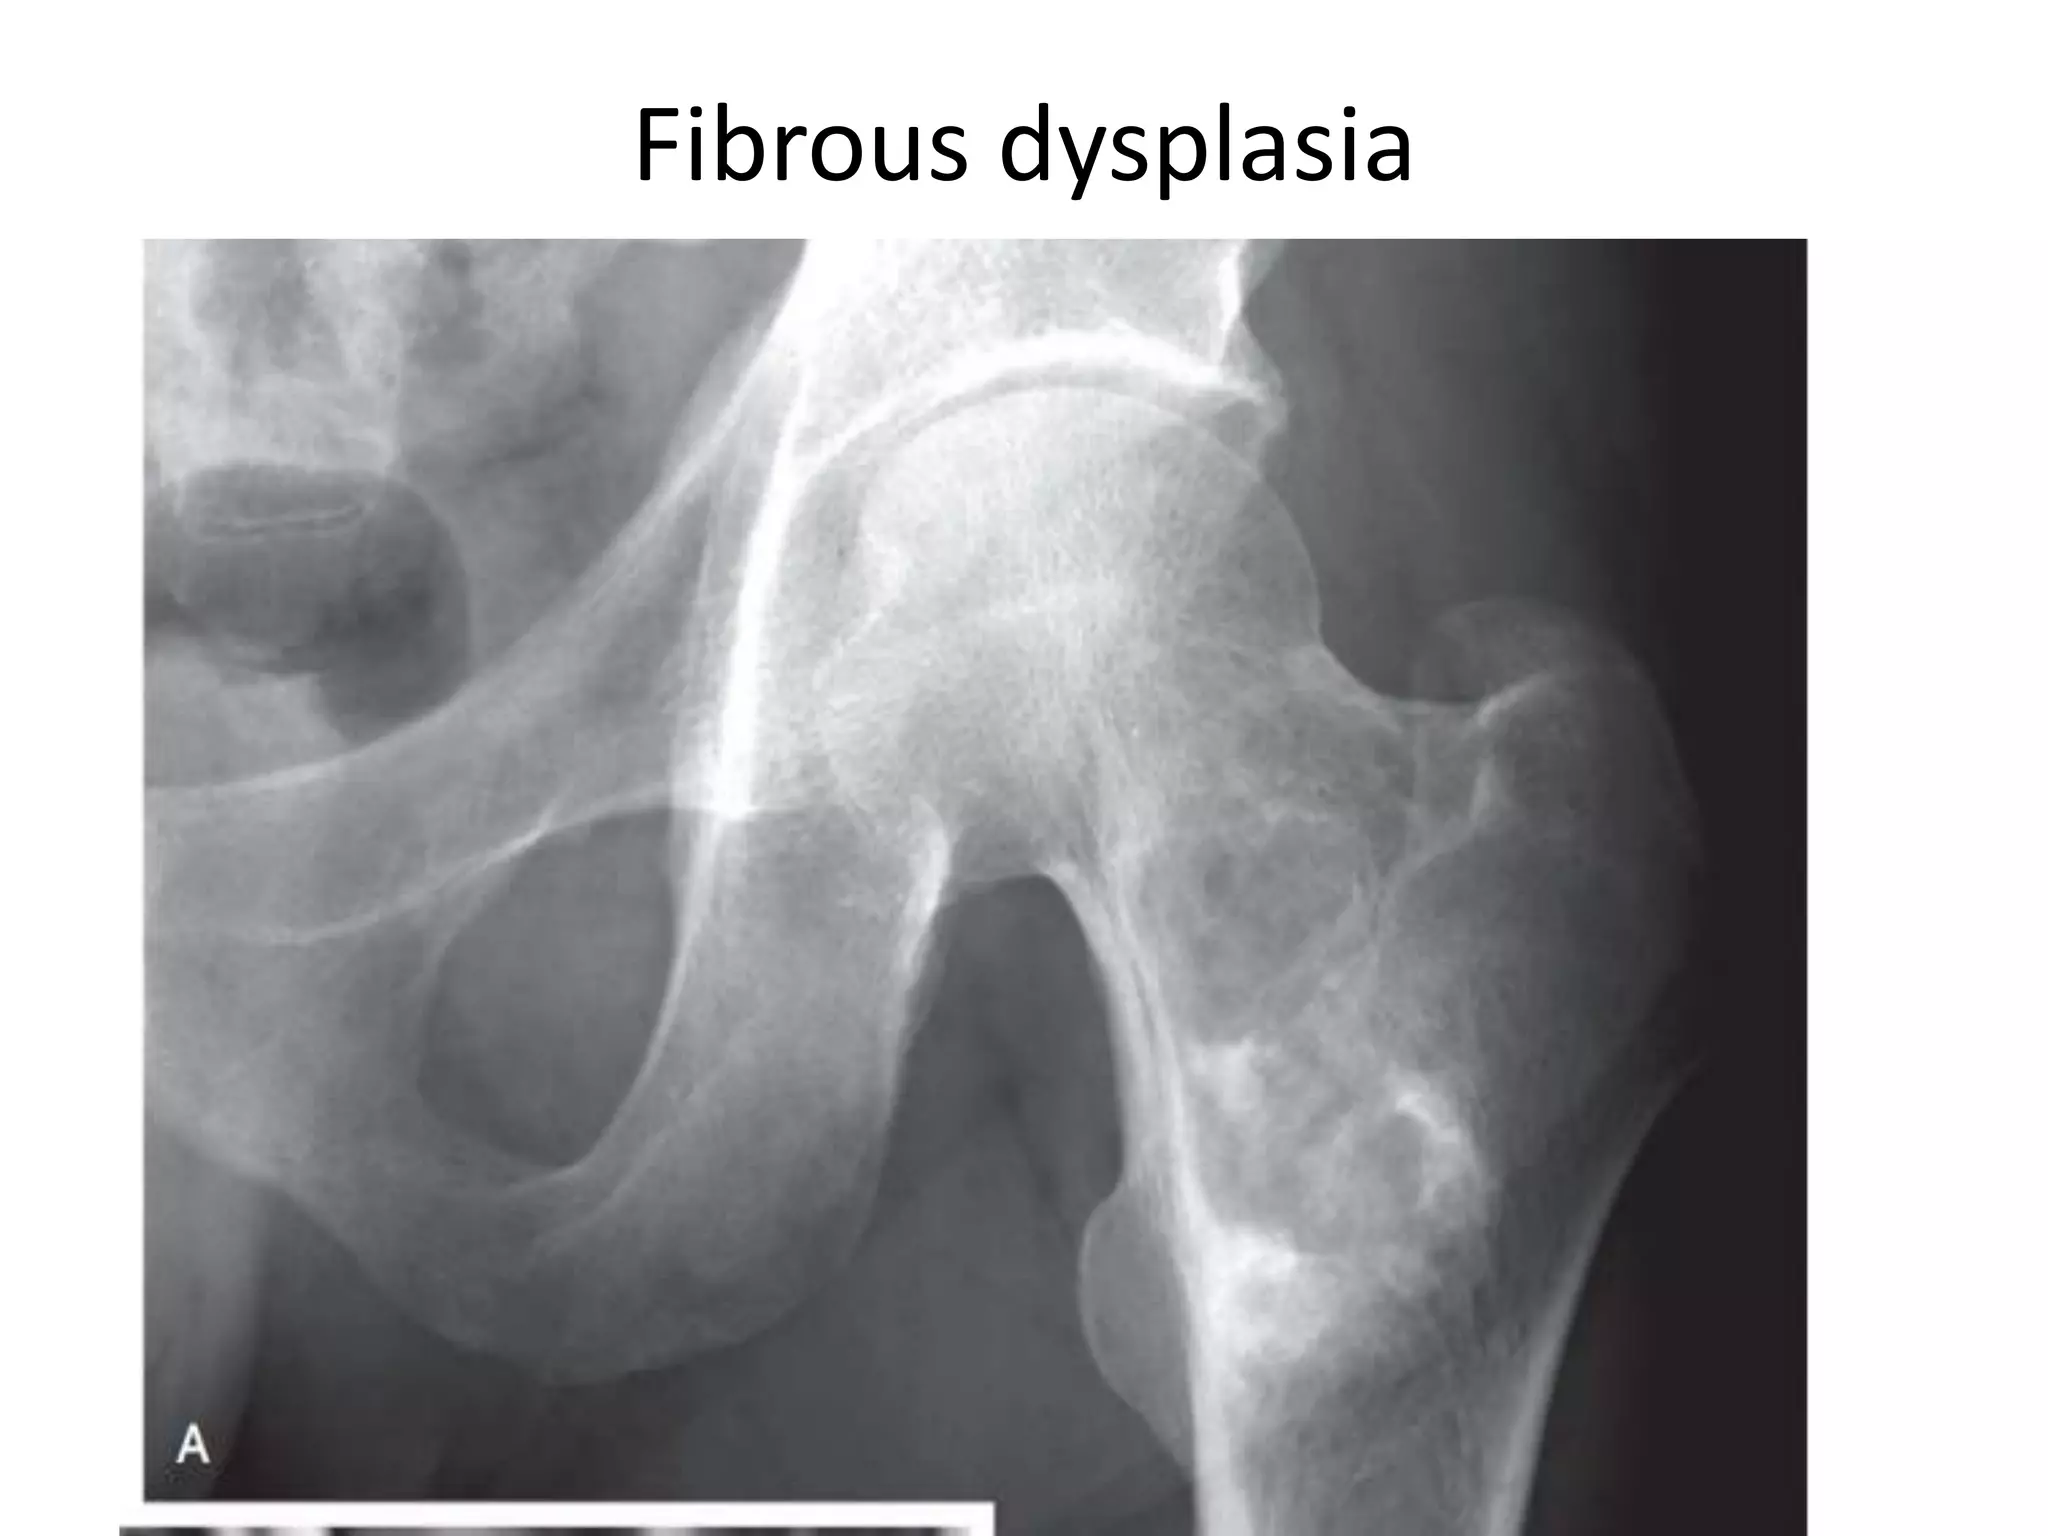

FIBROUS DYSPLASIA

• Fibrous dysplasia is a developmental anomaly of

bone formation. The hallmark is replacement of

normal bone and marrow by fibrous tissue and

small, woven spicules of bone.

• Fibrous dysplasia can occur in the epiphysis,

metaphysis, or diaphysis.

• Mazabraud syndrome

• McCune-Albright syndrome

• The disease usually manifests during the first

three decades of life (approximately 70% of

cases).

• The radiographic appearance is characteristic,

with the lucent area having a granular,

ground-glass appearance with a well-defined

sclerotic rim

• Characteristic deformity in proximal femoral

fibrous dysplasia is the shepherds crook

deformity.

• Histology: Demonstrates mixture of benign

proliferating fibroblastic cells within islands of

woven bone which characteristically appear in

a chinese letter formation.

• Malignant transformation 0.5 to 5 percent.

• Small lesion require no treatment.

• Surgical treatment is indicated when

significant deformity or pathological fracture

occurs or when significant pain exists.

• Deformities corrected by osteotomy with

internal fixation.